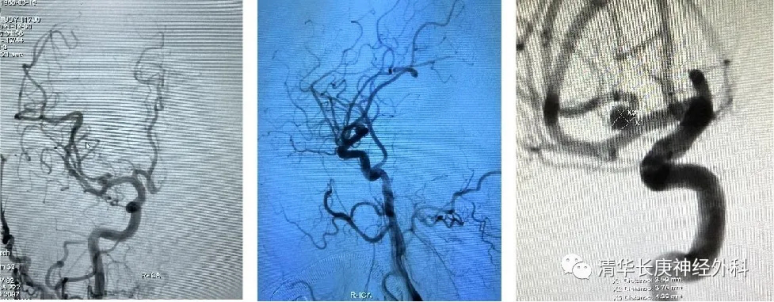

右侧MCA分叉处动脉瘤,主要累及上干载瘤动脉动脉瘤大小约:3.8*4.4mm

栓塞术毕正侧位造影